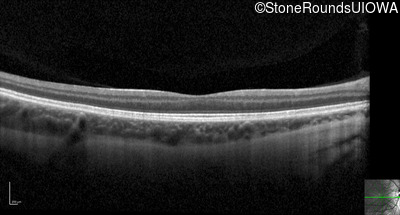

Optical Coherence Tomography - Right - 20/125

Exemplar / OCT Stack

OCT Stack